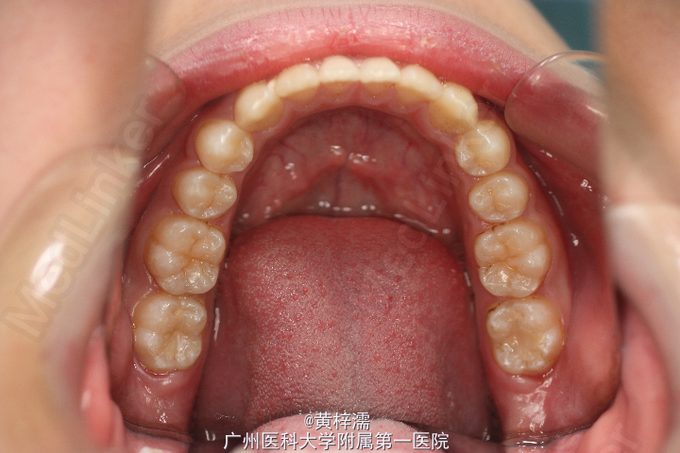

面部基本对称,无露龈笑,笑容不自然。直面型,面中1/3高度与面下1/3高度基本相等。下颌后缩,颏部发育稍不足。上中线与面中线一致,下中线稍右偏0.3mm。左侧磨牙关系中性,无尖牙关系。22,24间前庭沟下方可见鼓起,扪及23,磨牙覆盖正常。右侧磨牙关系中性,尖牙关系1/4远中,磨牙覆盖正常。上牙弓卵圆形,23缺牙间隙8.5mm,13宽度为8.5mm。口腔卫生可,未见牙体、牙周疾病,颞下颌关节检查未见异常。